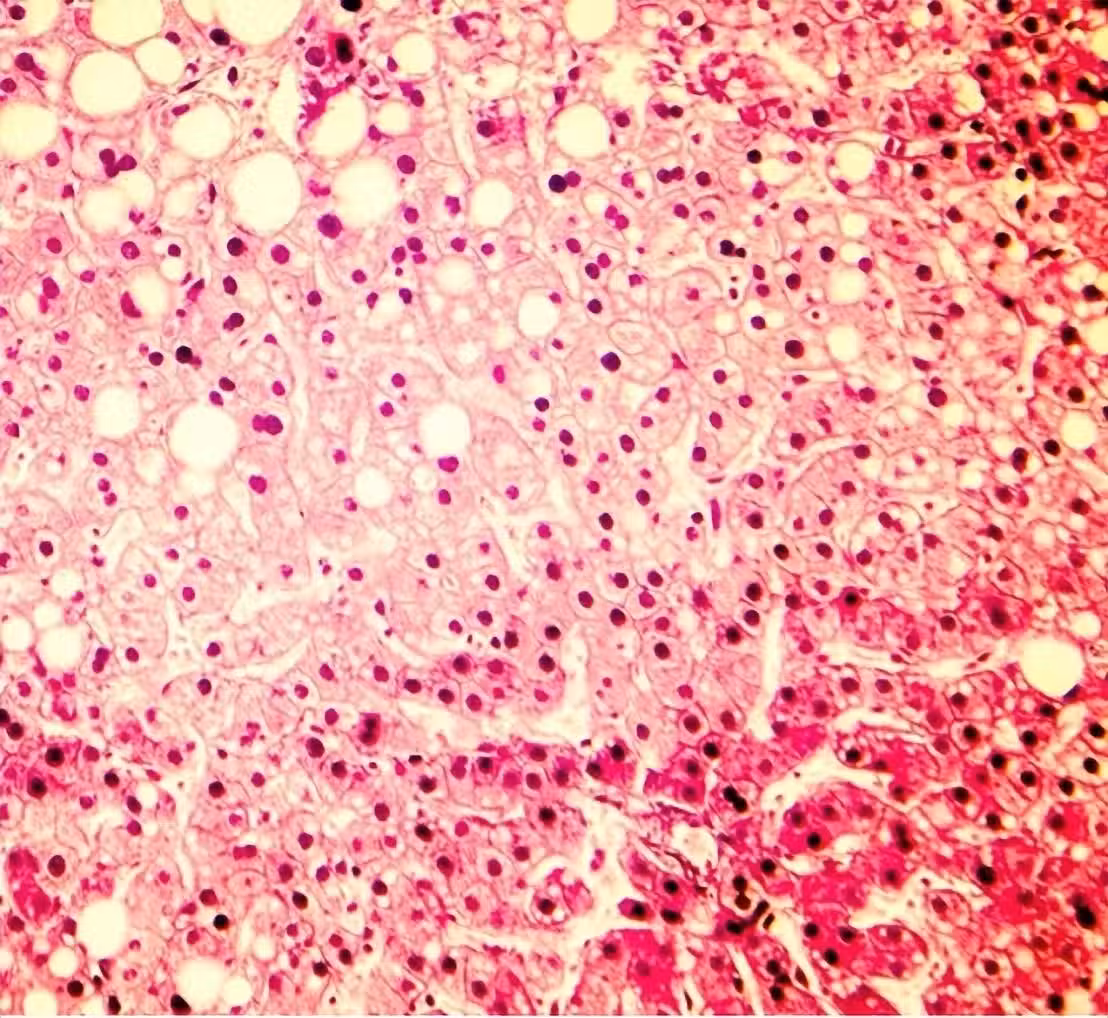

再次提醒:「3種食物」多吃容易堵塞血管 中老年人再愛吃都要「管住嘴」:防止中風

沈玉琳血癌!「白血病的來源」可能潛伏在你家!回家檢查一下,趕緊扔掉吧

一家四口「連患白血病」!醫揪元兇這家常菜「甲醛爆表400倍」…網嚇瘋:我昨天才吃